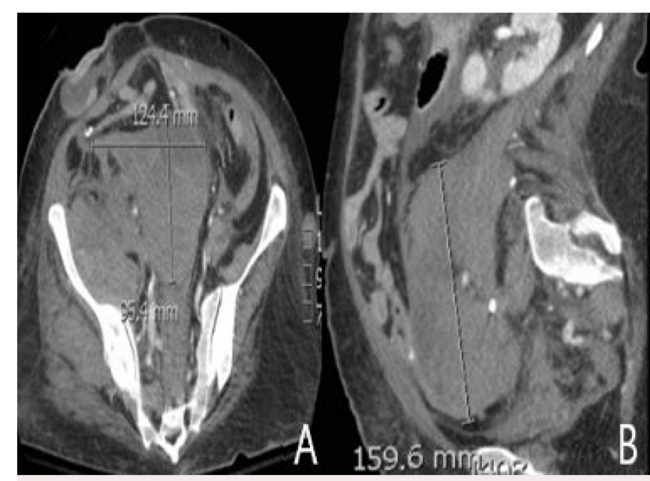

A 46-year-old woman with history of pulmonary embolism (PE), cecal perforation, and ostomy 5 months earlier presented to the emergency department with dyspnea, paleness, and hypotension. She started experiencing right lower quadrant pain 2 days earlier, which radiated to the right leg. She did not have cough, fever, blood in stool, or increased output from the ostomy. Vitals were remarkable for hypotension and tachycardia. Physical examination was remarkable for poor communication, distended abdomen without fluid wave, a subcutaneous firm area in the left lower quadrant, and bruising skin on the abdomen. Ostomy was clean without any bleeding. Labs were remarkable for creatinine, 1.33 (baseline 0.4); lactate, 24.1; white blood cells, 44,900; hemoglobin, 5; hematocrit, 16.3; mean corpuscular volume, 95.3; red cell distribution width, 18.8; platelets, 418; prothrombin time, 21.7; and partial thromboplastin time, 50. The patient was given fluids, norepinephrine, and vasopressin. Due to potential sepsis, she was given vancomycin and piperacillin/tazobactam, and several cultures were obtained. Culture results were negative. Chest X-ray was normal, and computed tomography scans of the abdomen and pelvis (Figure 1) showed findings consistent with massive retroperitoneal hemorrhage, including:

1. large retroperitoneal hematoma (Figure 1A and Figure 1B);

9. retroperitoneal hemorrhage extension into the right iliacus (Figure 1C) and right psoas muscles to the level of the lesser trochanter of the femur.